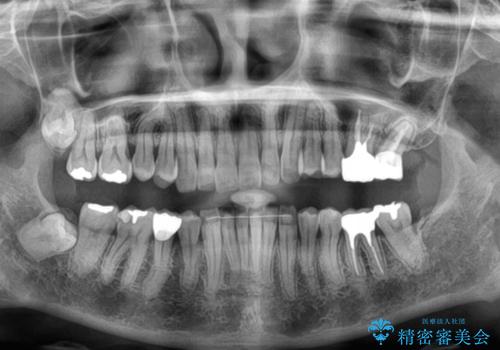

- 奥歯が咬めないくらいに痛いとのことで来院された患者様です。

痛みの強い歯は、歯髄組織が強い炎症を起こしており、神経を取り除く必要であったため、速やかに根管治療を行いました。

その後、オールセラミッククラウンにて補綴治療を行う予定でしたが、処置した歯以外にも治療が必要と思われる歯があったり、デコボコした歯列も気になるとのことで、患者様希望によりインビザラインにてマウスピース矯正を行うこととしました。

まずは矯正治療前に必要なむし歯処置を行い、その後矯正治療を行ってから、最後にオールセラミッククラウンなどで補綴治療を行うこととしました。

咬合力が非常に強く、全体的に歯が擦り減っている状態であったので、理想的な咬み合わせを達成することは難しく、また咬合力が強い方のマウスピース矯正は、思い通りに動かないことがあるため、ワイヤー矯正の方が望ましいように思えました。

治療途中で2年強、体調を崩されて通院ができなくなってしまったため、必ず通院が必要なワイヤー矯正ではなく、マウスピース矯正で結果的には無事に治療を終えることができました。